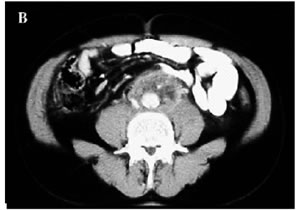

Figura 1. A-C: Tc spirale con MdC; evidenza di tessuto fibroso in sede retroperitoneale disposto attorno all'aorta,alla vena cava inferiore e alla biforcazione iliaca.(Da referenza 30)